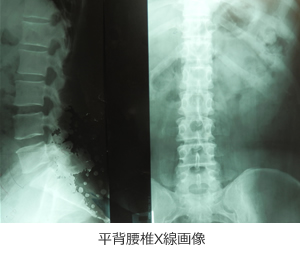

「前に転位した肩甲骨」「円背」「凹背」「凹円背」「側彎(片肩の偏り・歪み)」

「偏平足」「正常」に分類されます。